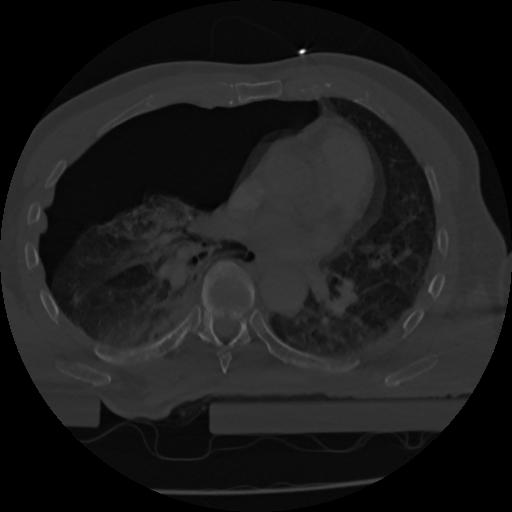

22 ANGIO,CE,Vol,0.5,ANGIO,,